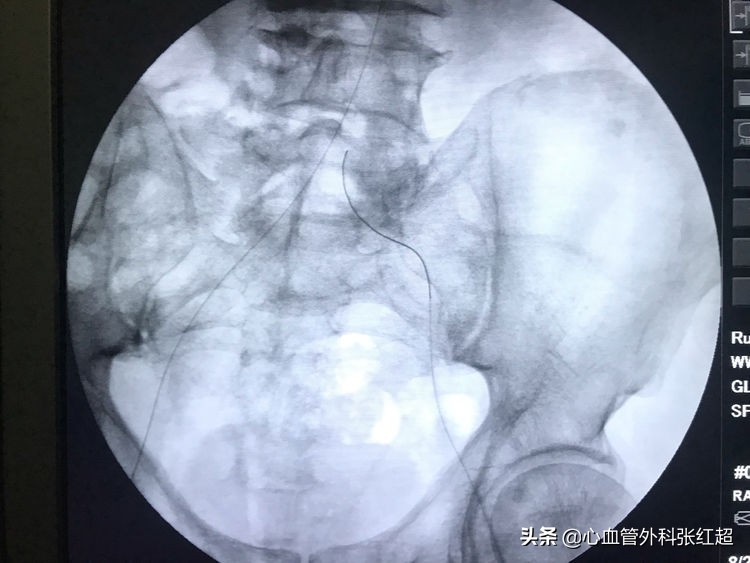

送入小球囊扩张,目的:①预防出血;②预防血栓脱落。

扩张时一定注意保持外鞘位置,避免血肿形成。

扩张中患者有痛应终止,防心弯曲部分球囊肩撕性撕裂。